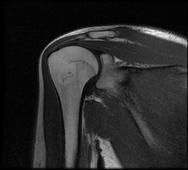

Osteokondrom

Egzositoz adı da verilir. Kemiğin dış yüzünde adeta kemik çıkıntısı gibi bir görüntü verir. Çıkıntının üzerinde oluşan kıkırdak kepten büyümesini sürdürür. Osteokondromlar saplı veya sapsız olabilirler. Saplı olanlar daha yaygındır.Osteokondromlar tek ya da çoklu (Hereditermultipleosteokondromatozis) olurlar. Herediterosteokondromlar genetik olarak geçer. Osteokondrom 10-20 yaş arasında ve erkeklerde daha sık görülür. Diz çevresi ile omuz çevresinde daha çok görülür.

MRI, yeni ortaya çıkan ağrı, yumuşak doku invazyonu yada kondrosarkoma dönüşme şüphesi olan olgularda istenir. MRI’da kıkırdak kep kalınlığı erişkinde 1 cm’den, çocuklarda 2 cm’den daha fazla ise kondrosarkom lehine düşünülebilir. Parostealosteosarkom da ayırıcı tanıda unutulmamalıdır. Büyümenin tamamlanması ile osteokondromda gelişimini tamamlamış olur.

Tedavide hasta takip edilir; şayet komşu damar ve sinire bası yapıyorsa, sonradan ağrı gelişirse, kıkırdak kep kalınlığı erişkinde 1.5 cm, çocuklarda 2 cm den fazla ise eksize edilir. Tedavi lezyonun blok olarak rezeke edilmesidir.